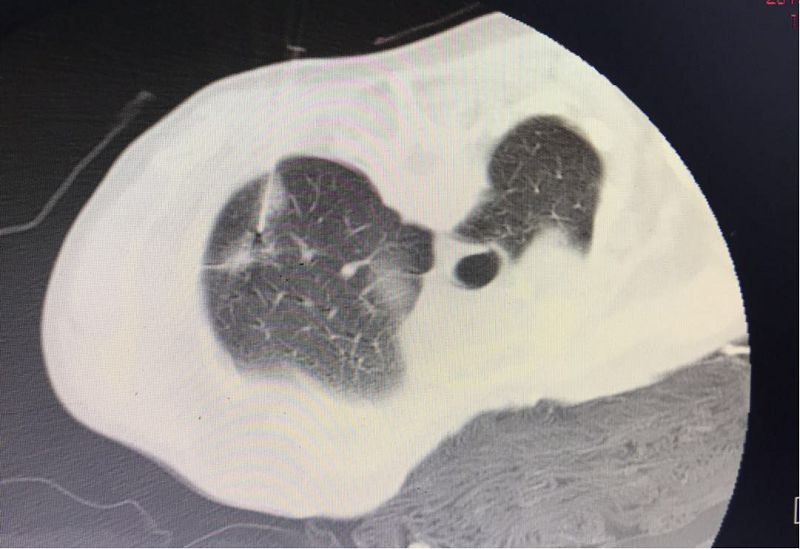

左上肺后段混合磨玻璃小結(jié)節(jié)

小結(jié)節(jié)精準(zhǔn)穿刺,一針到位,正中靶心。

混合性磨玻璃結(jié)節(jié)影密度低,縱隔窗不顯影,穿刺定位是在肺窗下,縱隔窗僅見穿刺針。